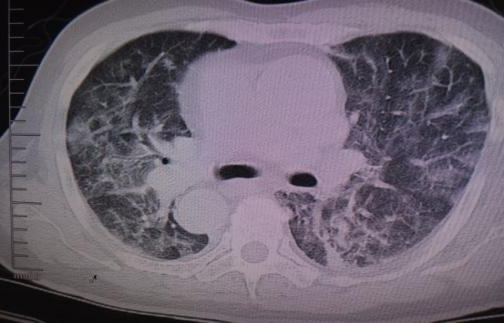

5.重症流感:流感病毒感染引起肺炎、发展为重症疾病[呼吸衰竭、急性呼吸窘迫综合征(acuterespiratory distress syndrome,ARDS)、感染性休克、心肌受累、中枢神经系统受累、多器官功能衰竭]或慢性基础疾病加重而需要住院治疗的患者。对于人感染新亚型流感(如尚未广泛传播,且致病性、病死率或重症风险尚未明确的甲型流感病毒亚型)的感染者,即使未完全符合上述重症流感的判定标准,也应被视为重症流感病例。